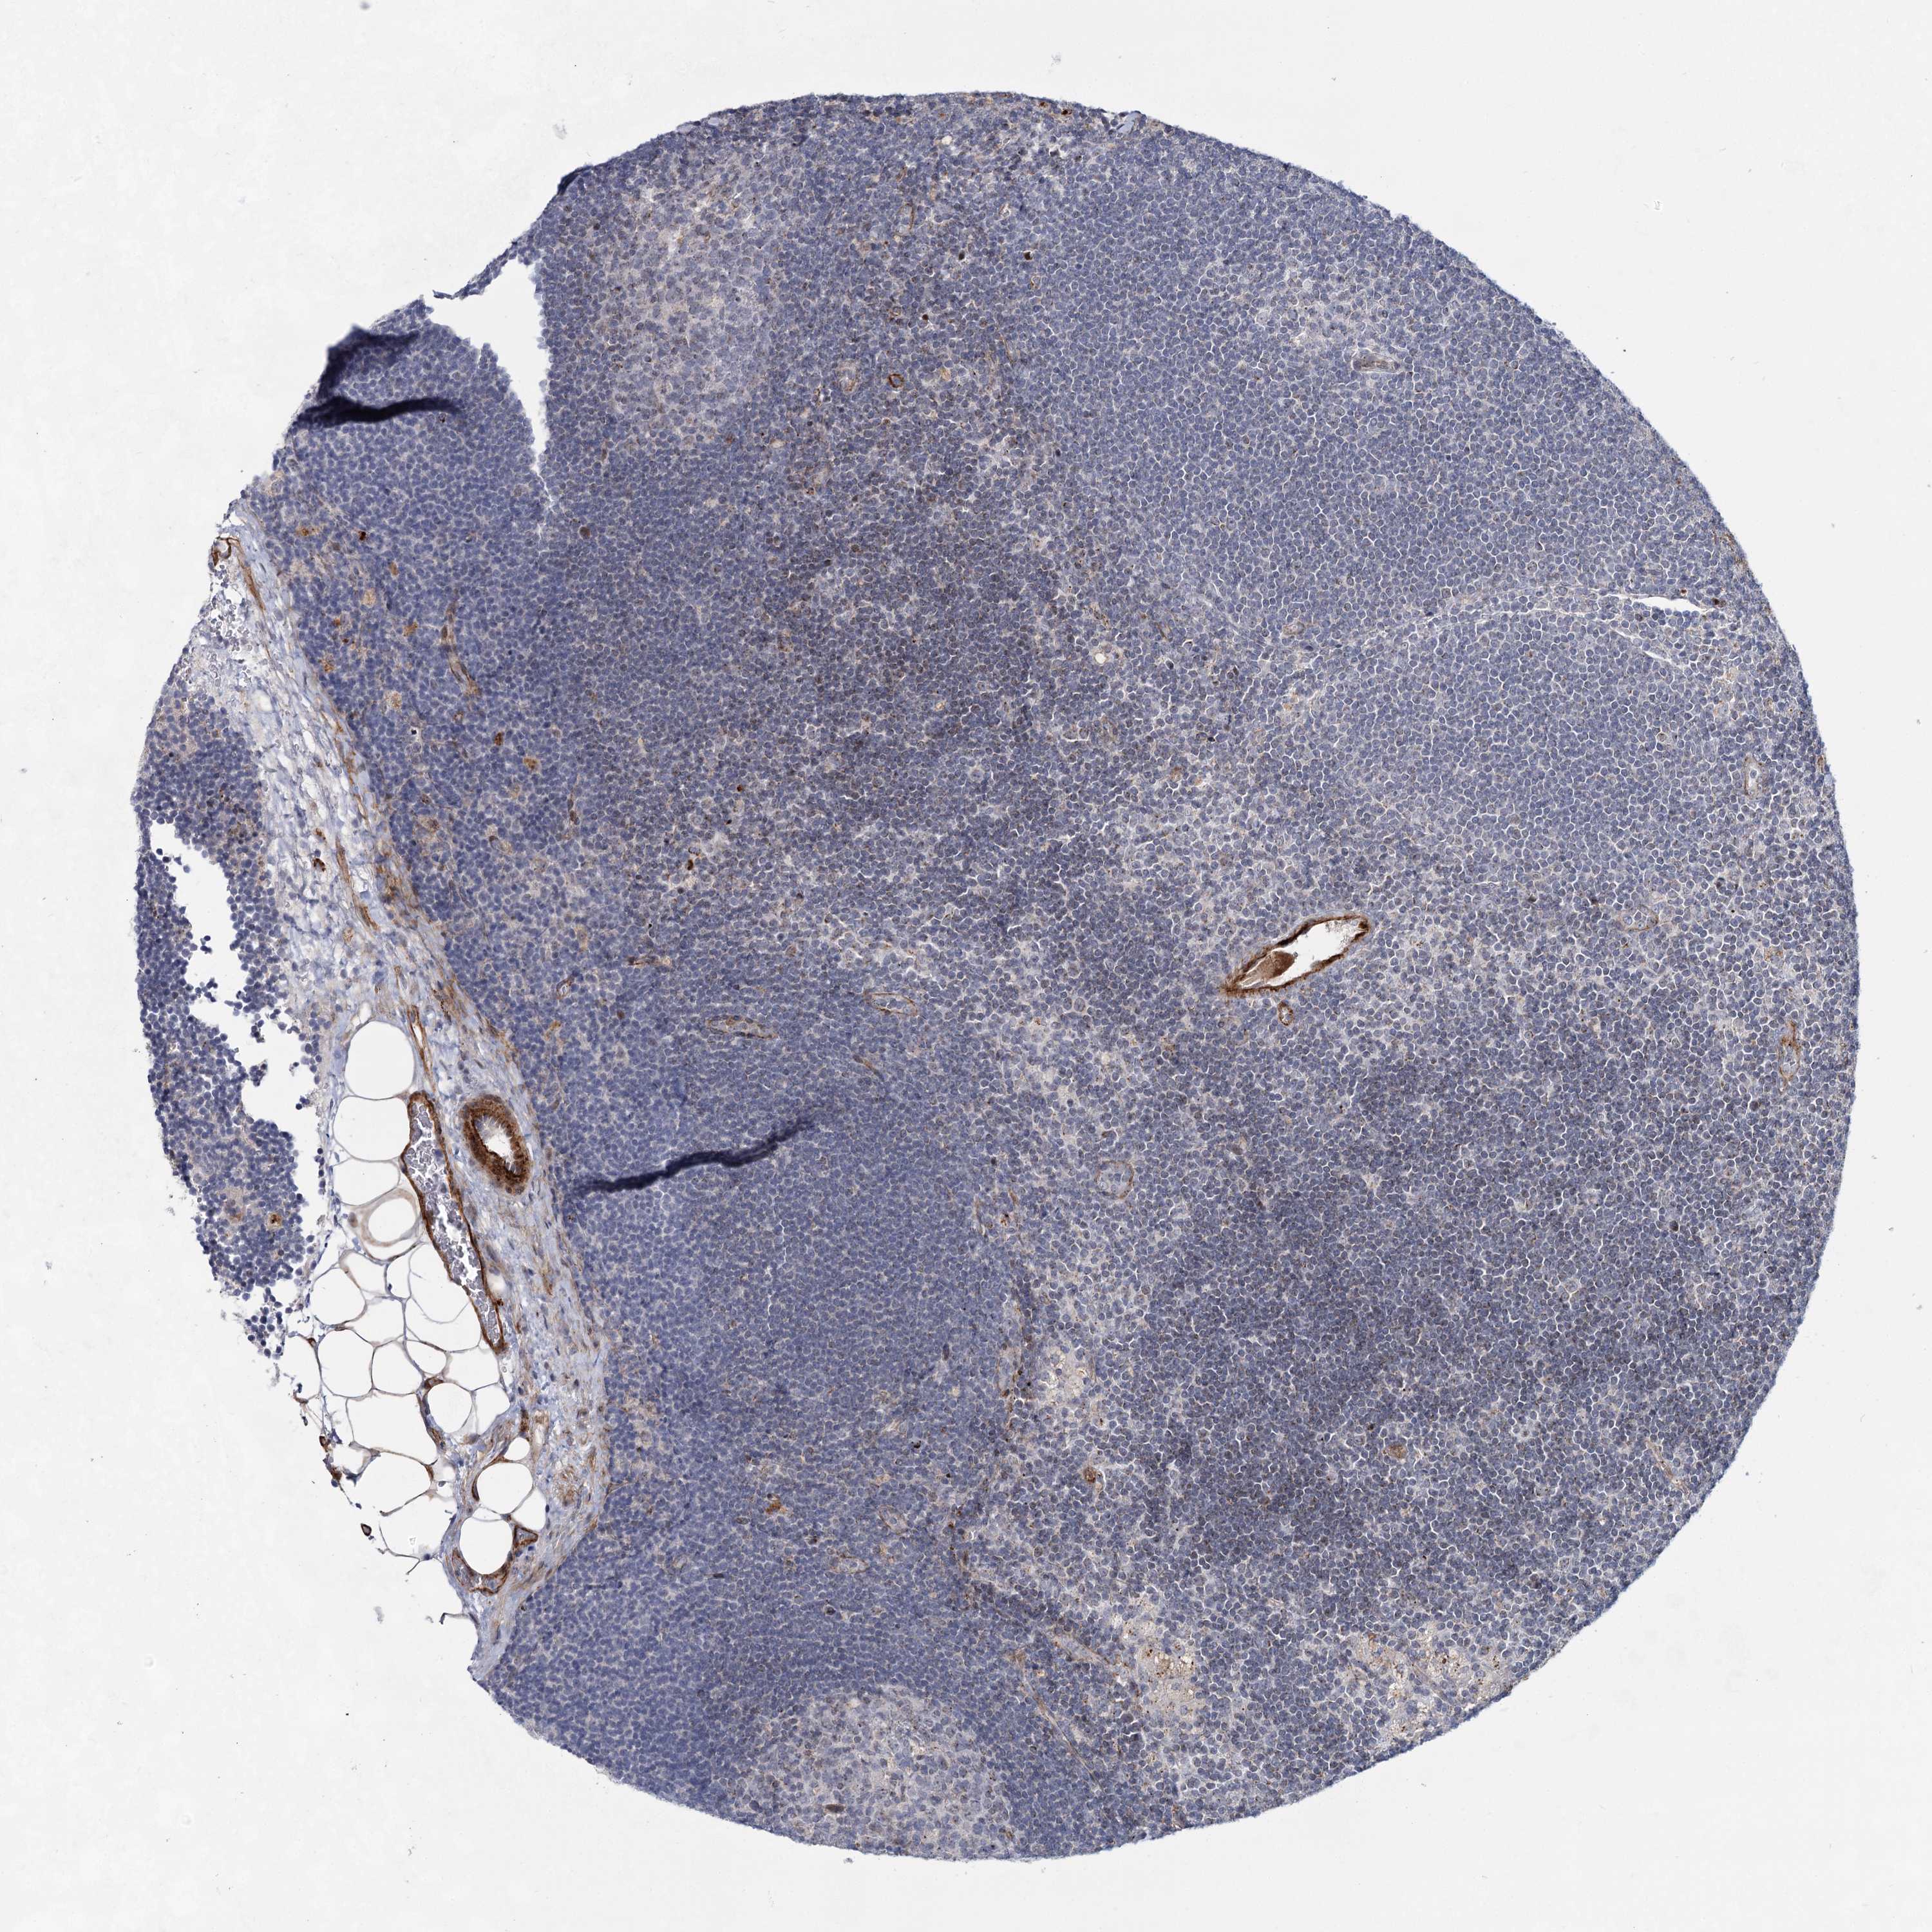

LYMPH NODE

Lymphoid tissue